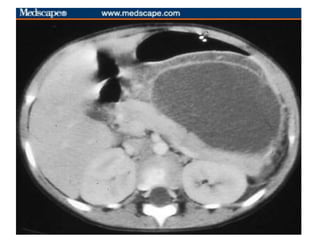

•CT Abdomen with contrast:- phlegmon(inflammatory mass),

CT:

typical findings:

-focal or diffuse parenchymal enlargement

-calcifications may be seen within the parenchyma

-changes in density because of oedema

-indistinct pancreatic margins owing to inflammation

-surrounding retroperitoneal fat stranding

liquefactive necrosis of pancreatic parenchyma: lack of

parenchymal enhancement

Radiological Investigations

•CT : Most accurate (sensitivity 90-100%)